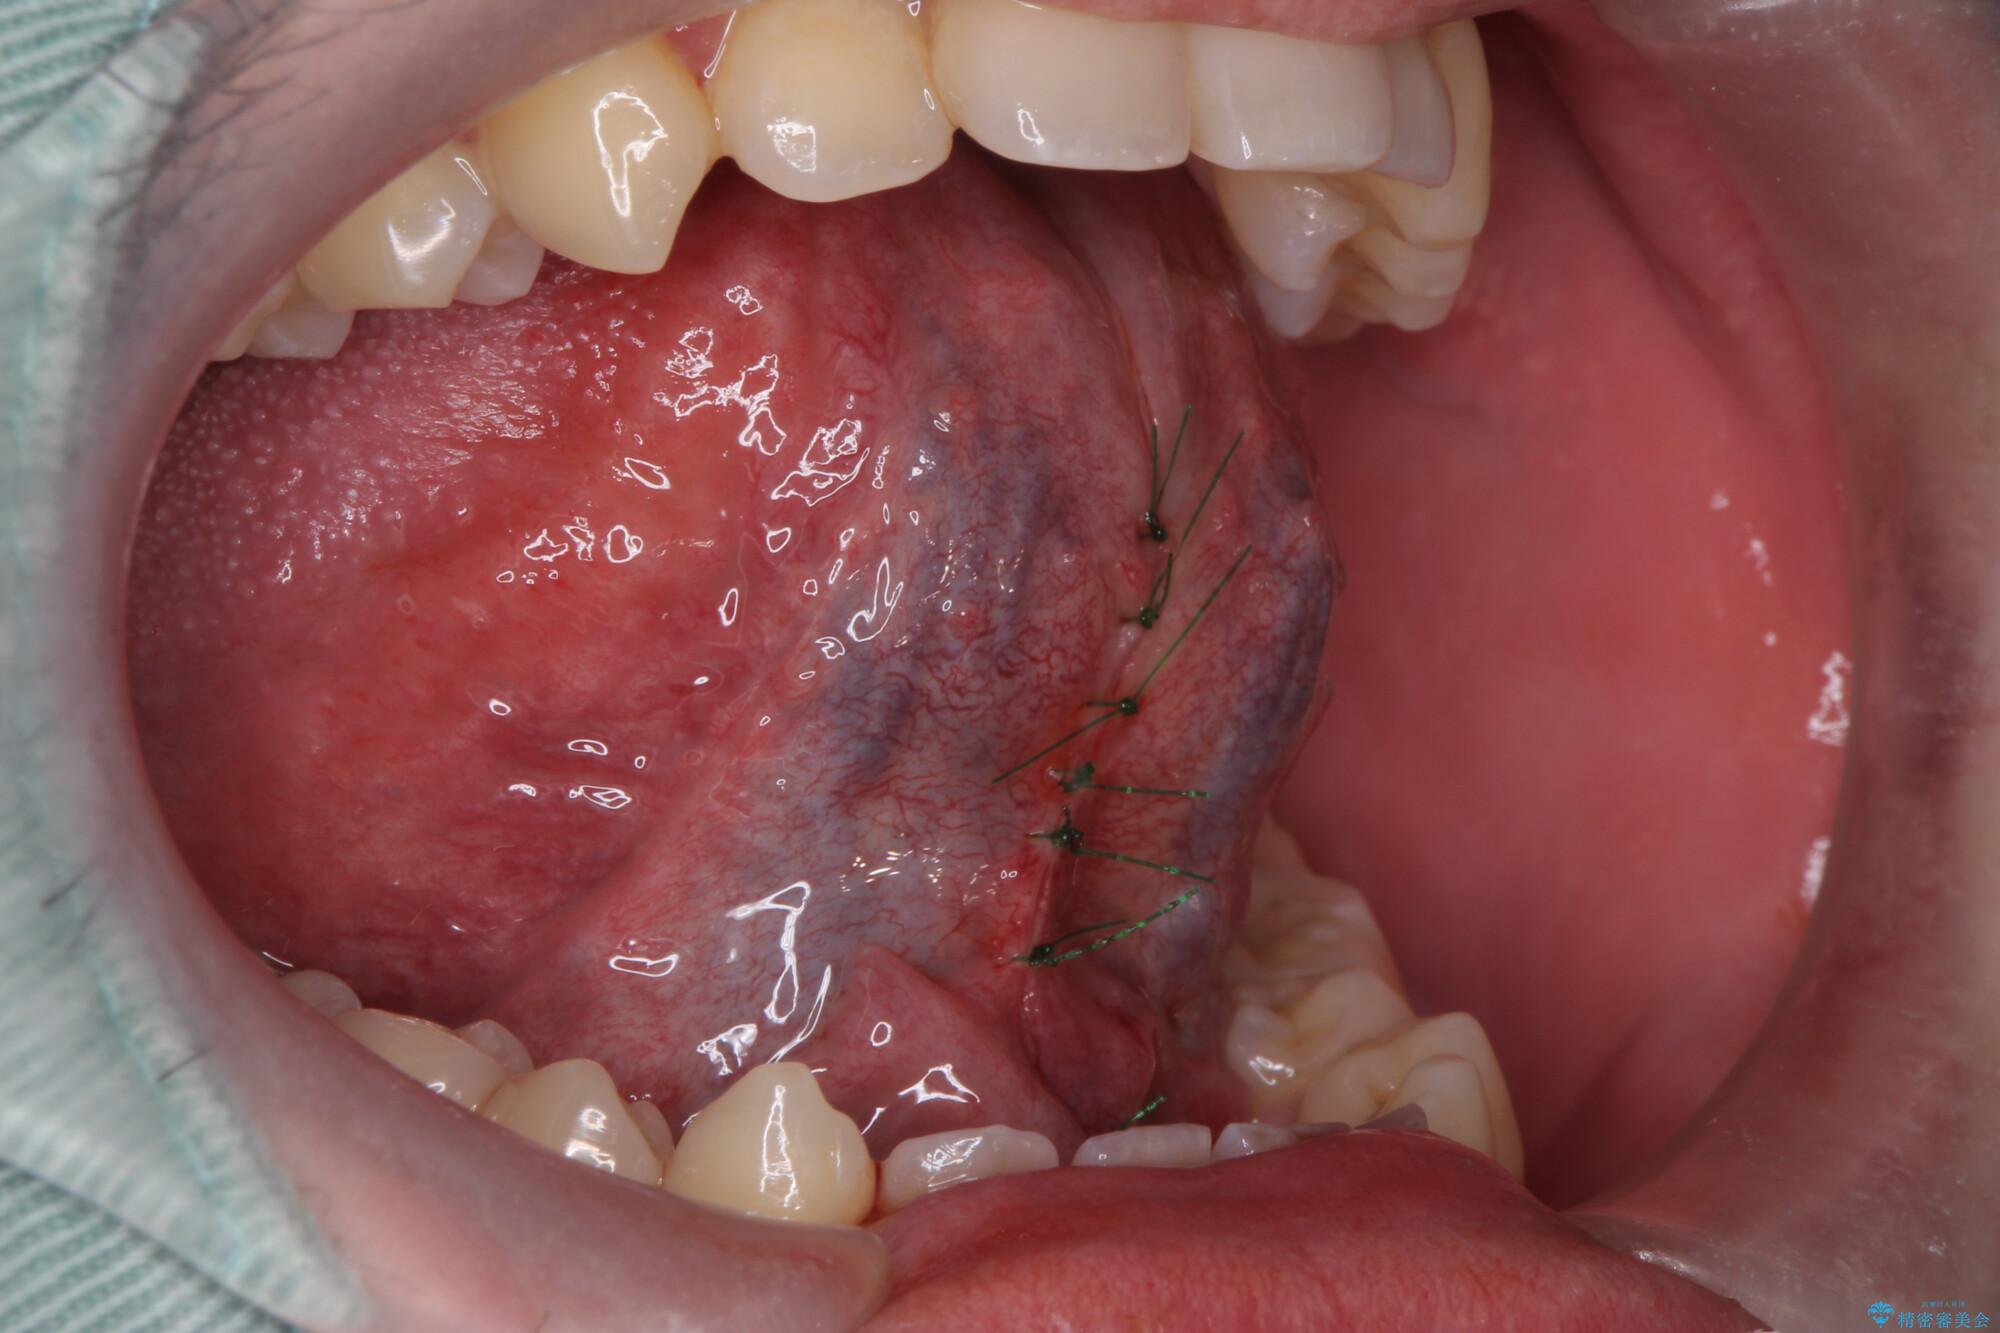

治療中

舌小帯を切除し滑舌を治したい 治療中画像 舌小帯を切除し滑舌を治したい 治療中画像